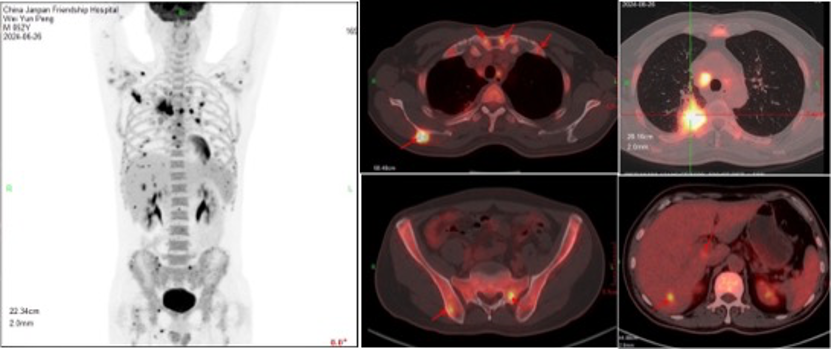

PET-CT检查:1.双肺上叶病变呈高代谢,全身多发淋巴结不同程度代谢增加,肝、脾及多骨高代谢灶,建议右肺上叶病灶穿刺活检,除外恶性肿瘤性病变。2.脾及骨髓弥漫代谢增加,考虑炎性继发改变。双肺内微小结节及双侧叶间胸膜结节样增厚,未见代谢增加,考虑良性可能;右肺下叶少许炎性病变;双肺气肿。心包少量积液。3.脂肪肝。前列腺内多发钙化。右肩关节周围炎。